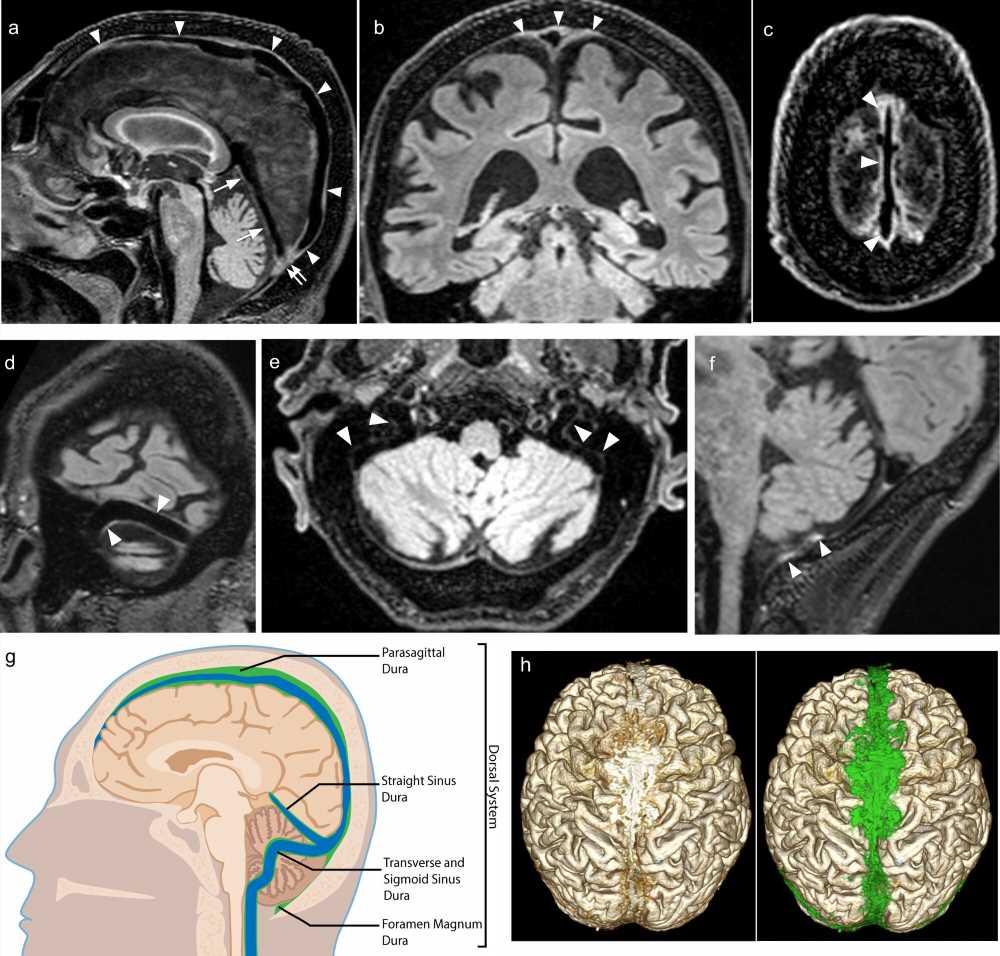

In this study, investigators were able to overcome this limitation and use MRI to visualize lymphatic vessels in the meninges without the need for contrast agent. Instead, the team used differences in the brain’s own protein content to create a gradient in contrast. Structures with low protein content appear dark and those with high protein content appear light, with high enough resolution to see intricate details.

This simple yet innovative approach enabled investigators to capture clear images of lymphatic vessels, with their high protein content—about 50-fold greater than that of CSF—as they connected areas within the brain to lymph nodes in the neck.